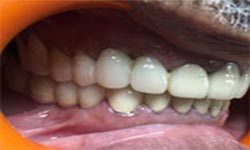

(9) Metal Ceramic Crowns

Before Treatment

After Treatment

Mr. Shiv Narayan Singh,aged 78yrs, came with a concern of multiple broken and mobile teeth with difficulty in chewing food. So, multiple RCTs followed by metal-ceramic crowns were delivered to the patient ,restoring his beautiful smile.